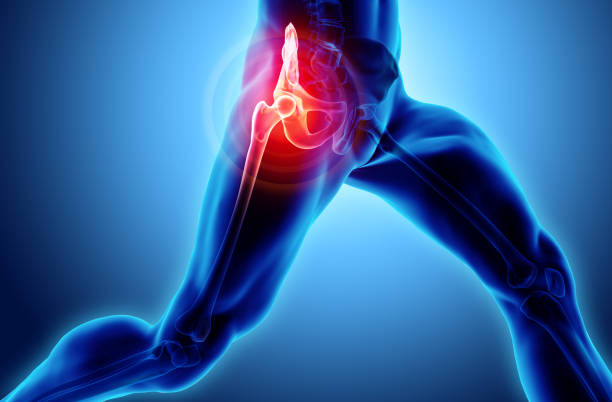

Joints Replacement

Hip Replacement Surgery

Osteoarthritis